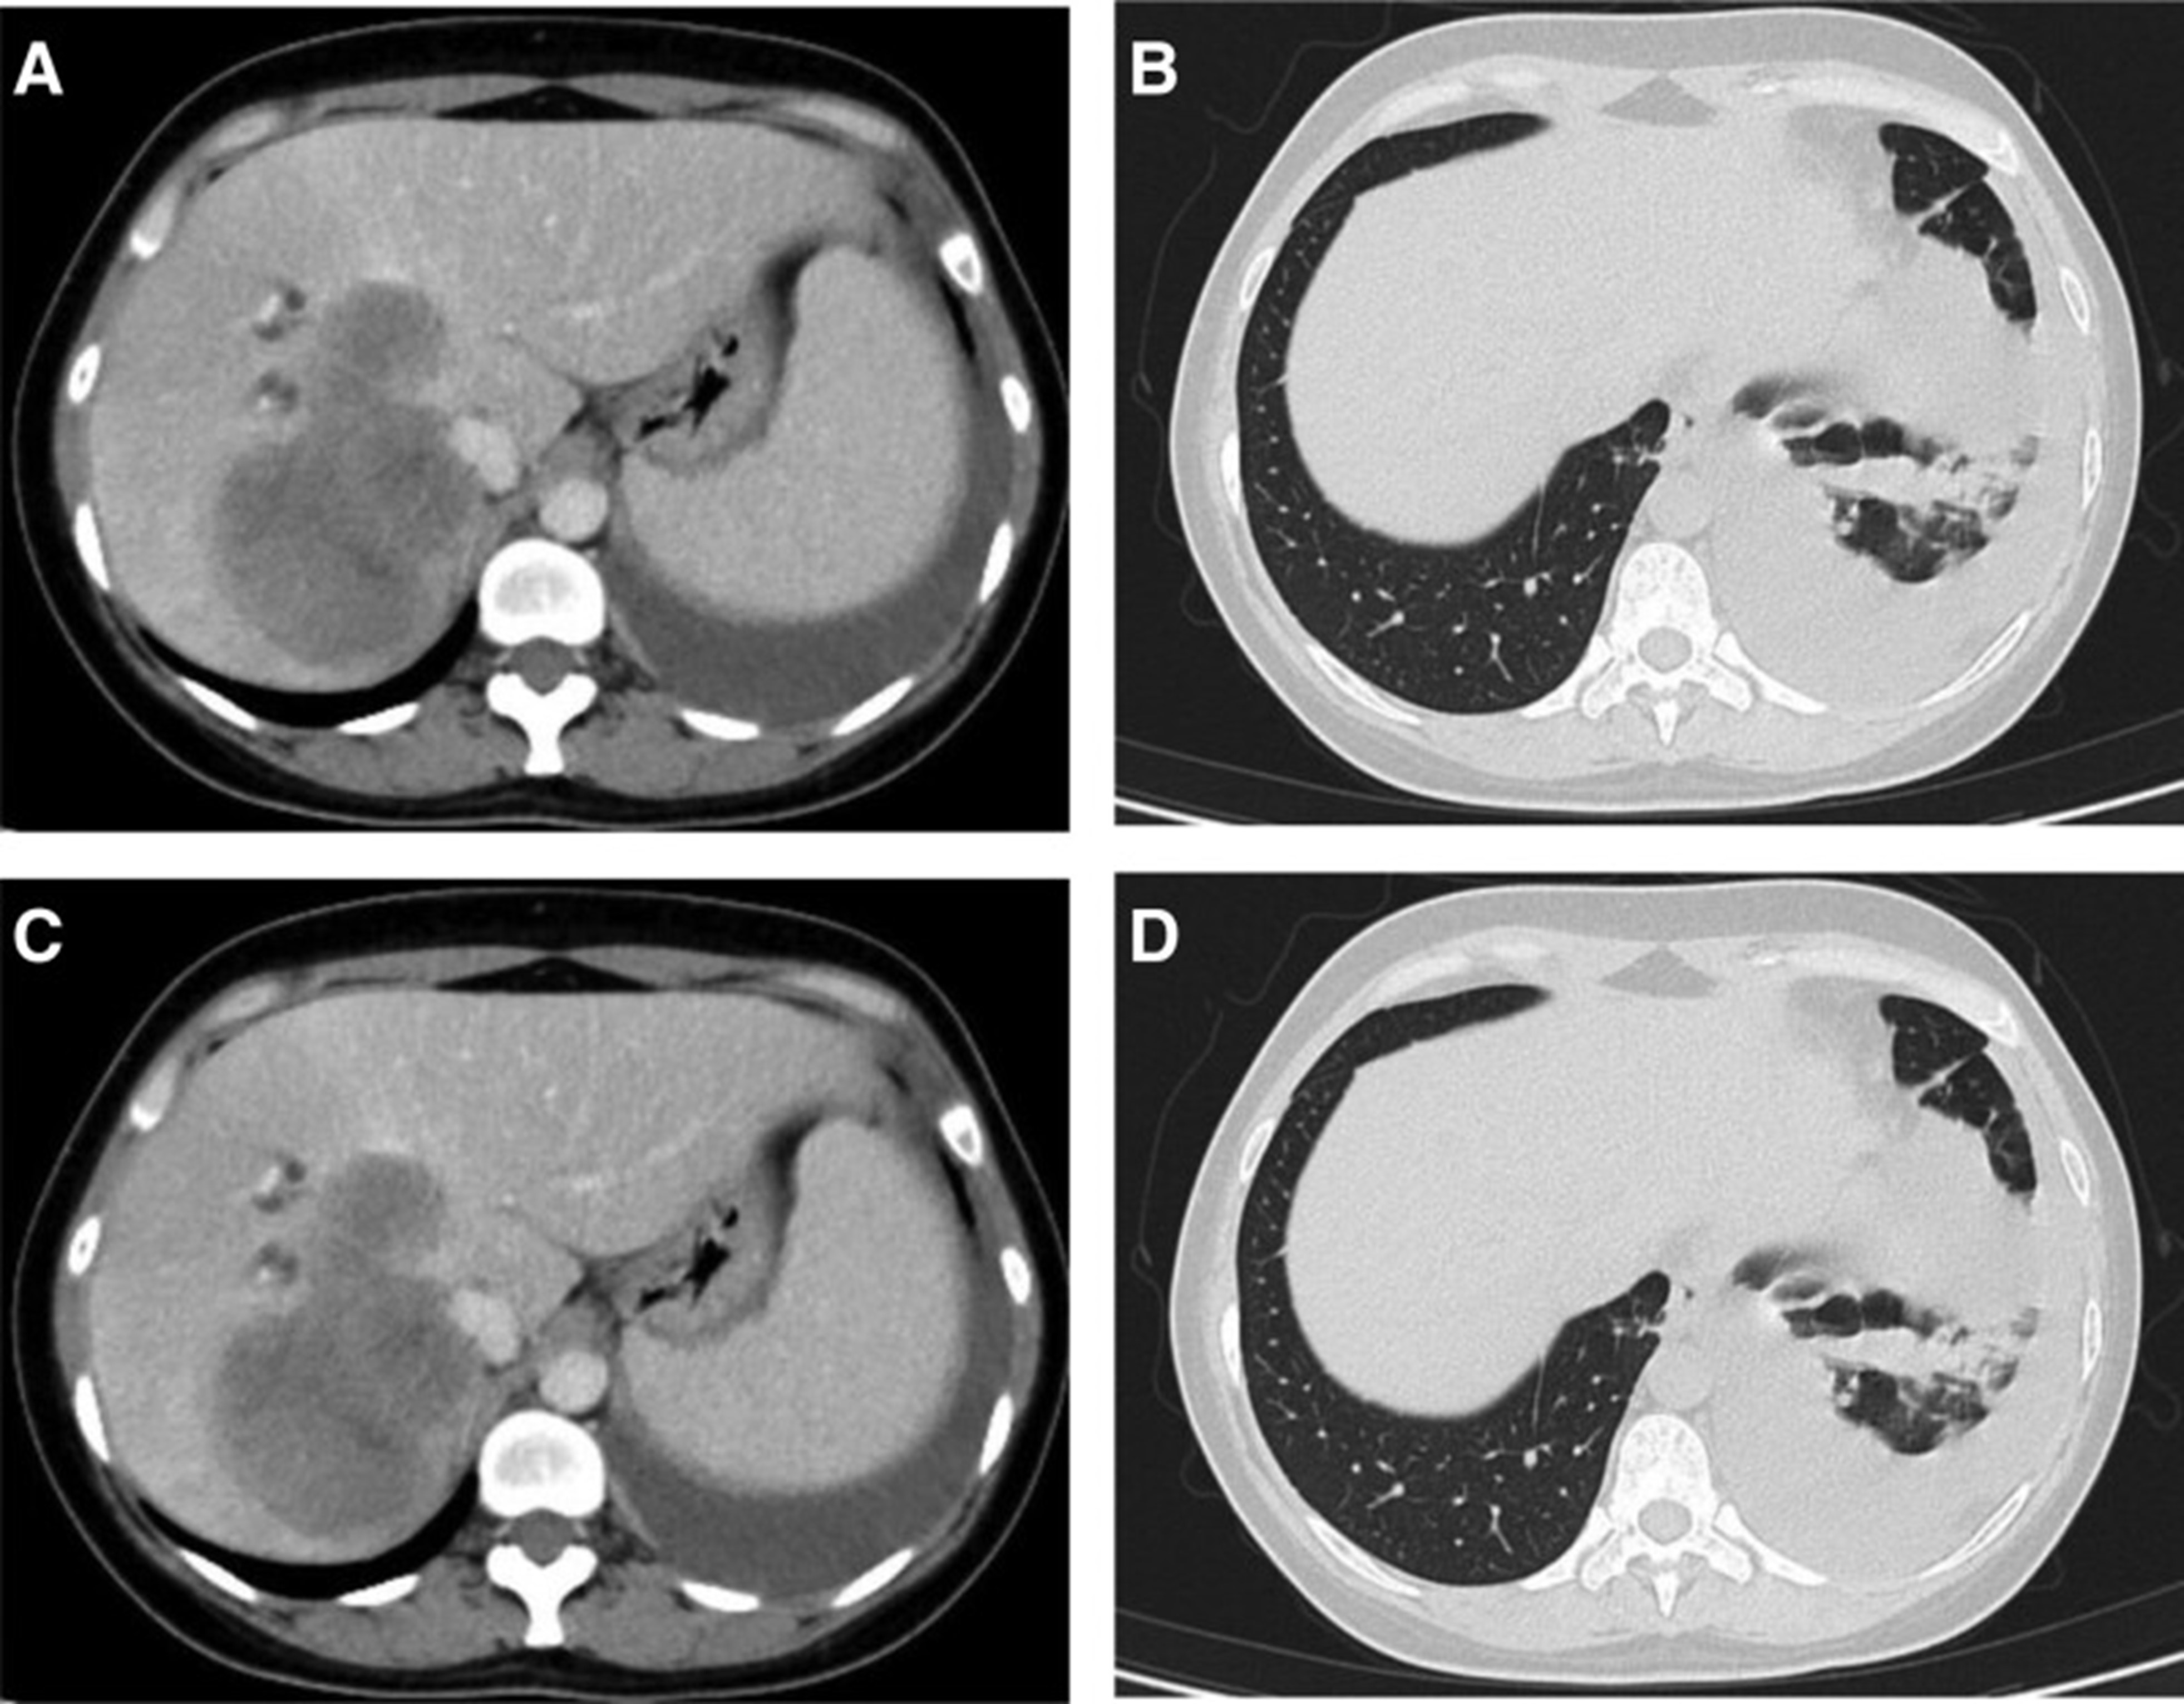

2020年4月,患者胸部CT示“双肺多发结节,纵隔及肺门多发肿大淋巴结;附着于肝右叶,略呈低密度肿块影”(图 1)。(图4A,4A、B)和腹部CT显示“肝脏多发肿块”(图1)。(图 4C)。骨扫描显示“身体多个部位的骨代谢异常增强”。2020年4月19日,对“右肝肿块和右锁骨上肿块”进行活检,病理指征(右肝肿块抽吸、右锁骨上肿块抽吸)为低分化腺癌。结合免疫组化结果,首先考虑的是肺腺癌转移。最终诊断为“IV期肺腺癌伴多发肝和骨转移”。基因检测显示“EML 4-ALK 融合,PD-L1 肿瘤阳性细胞数TPS 80%”(图 2)。(图1和和2)。

图 4:2020 年 4 月 (A-C) 和 2020 年 6 月 (D-F) 的 CT 扫描。CT = 计算机断层扫描。

2020年5月1日,患者开始口服艾乐替尼靶向药物进行治疗,2020年6月25日复查,确定治疗效果为PR(部分有效)(根据RECIST1.1)显示肺病灶和肝转移灶明显减少(图1)。(图 3D-F)。2020 年 8 月 27 日复查确定治疗效果为疾病进展(PD, progressive disease),根据 RECIST1.1显示肝脏病变变大(图 1)(图 4A-D)。进行了第二次肝活检,随后的病理学显示“(肝)低分化癌,结合免疫组织化学分析考虑肺腺癌转移”。组织活检进行了第二轮基因检测,结果显示“BRAFV600E 14.79%,EML 4-ALK fusion 14.47%”(图 1)(图 5)。2020年9月20日,对患者我以为用恩沙替尼联合达拉非尼靶向治疗。治疗开始后,患者出现明显发热、寒战、乏力和厌食。期间患者左侧出现大量胸腔积液,胸腔积液中脱落细胞为“非典型细胞,考虑为腺癌”。随后,该患者接受了 1 次胸腔内铂输注。

和 2020 年 8 月.jpg)

图 5:2020 年 6 月(A 和 B)和 2020 年 8 月(C 和 D)的 CT 扫描。CT = 计算机断层扫描。